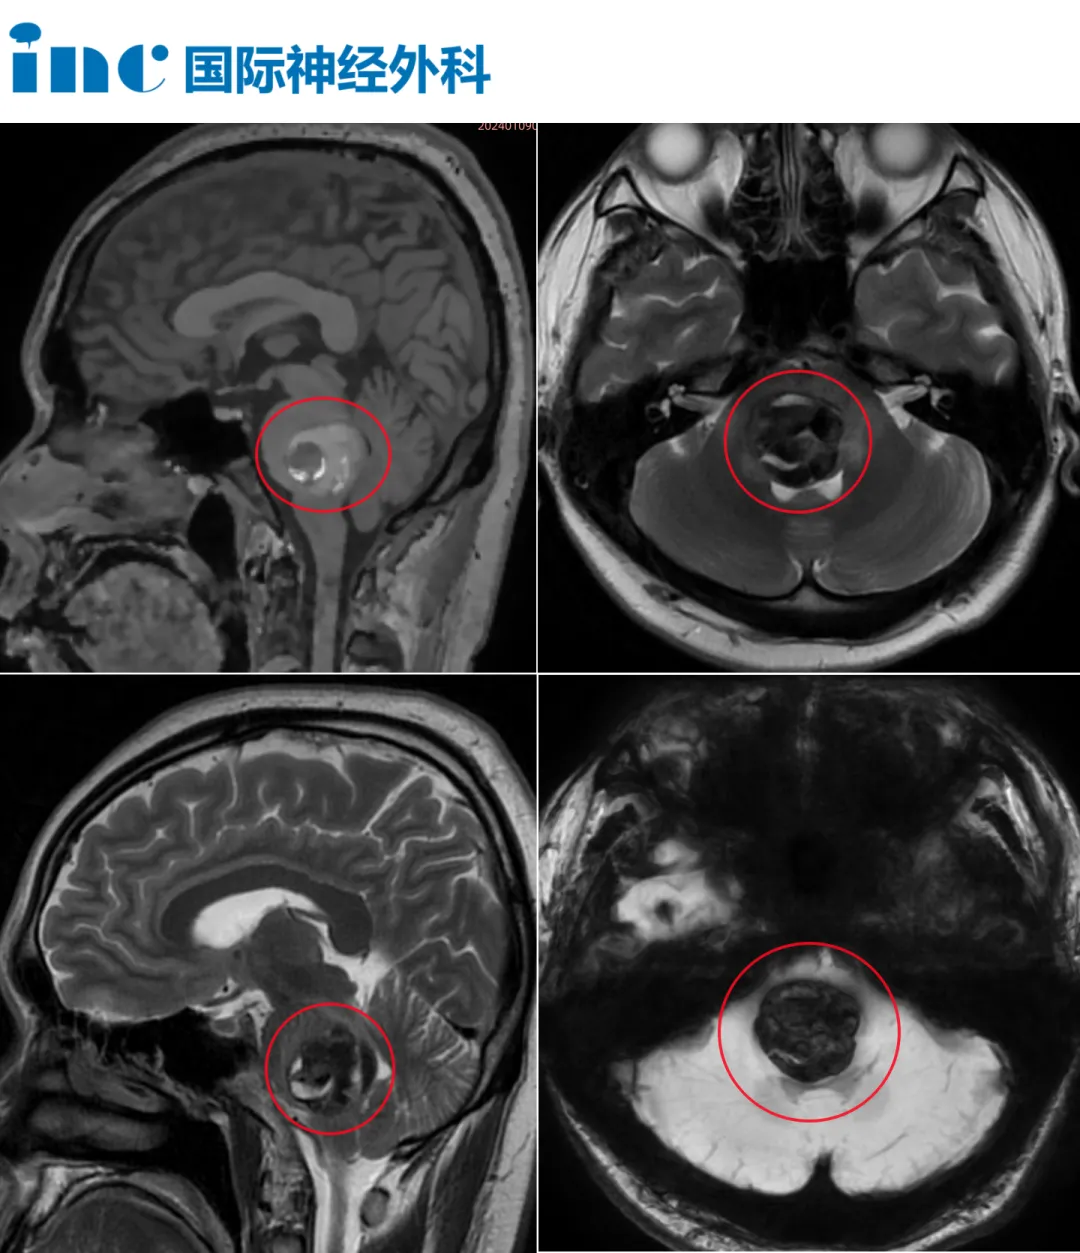

脑干出血情况危急! 仅10多天时间 身体麻木、面瘫、吞咽困难 听力下降、无法行走 术后当天时间,患者醒了! 术后仅1天,面瘫就缓解了 术后6天,可以独自行走! 脑干是手术...